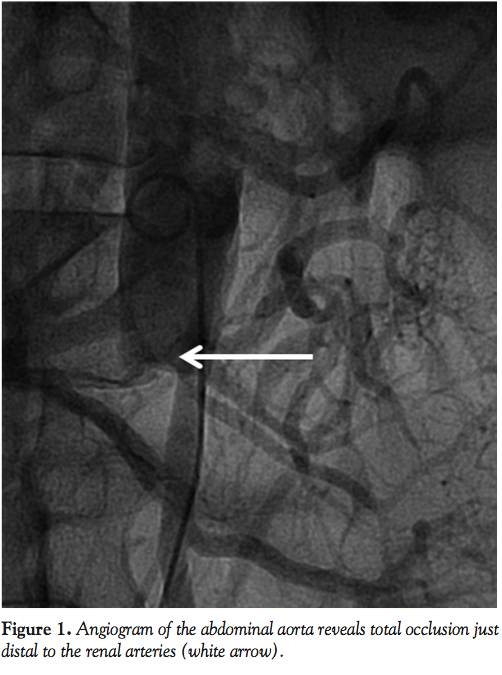

Figure 1 from Functional formula to determine adequate balloon diameter of simultaneous kissing